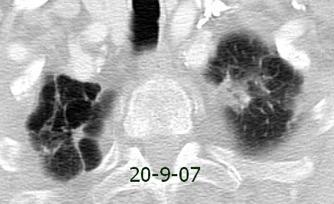

Síndrome de afectación postcardiaca (postcardiac injury)

Post infarto 1-7 % (Dressler)

Trauma cerrado Implantación marcapasos

Cirugía cardiaca. 17-31% (Post.pericardiotomía)

3707 pacientes 29 Derrames (0,78%) > de 25% del hemitórax

Todas menos 2 Izdos.

Angioplastia

By-pass coronario 21-10-03